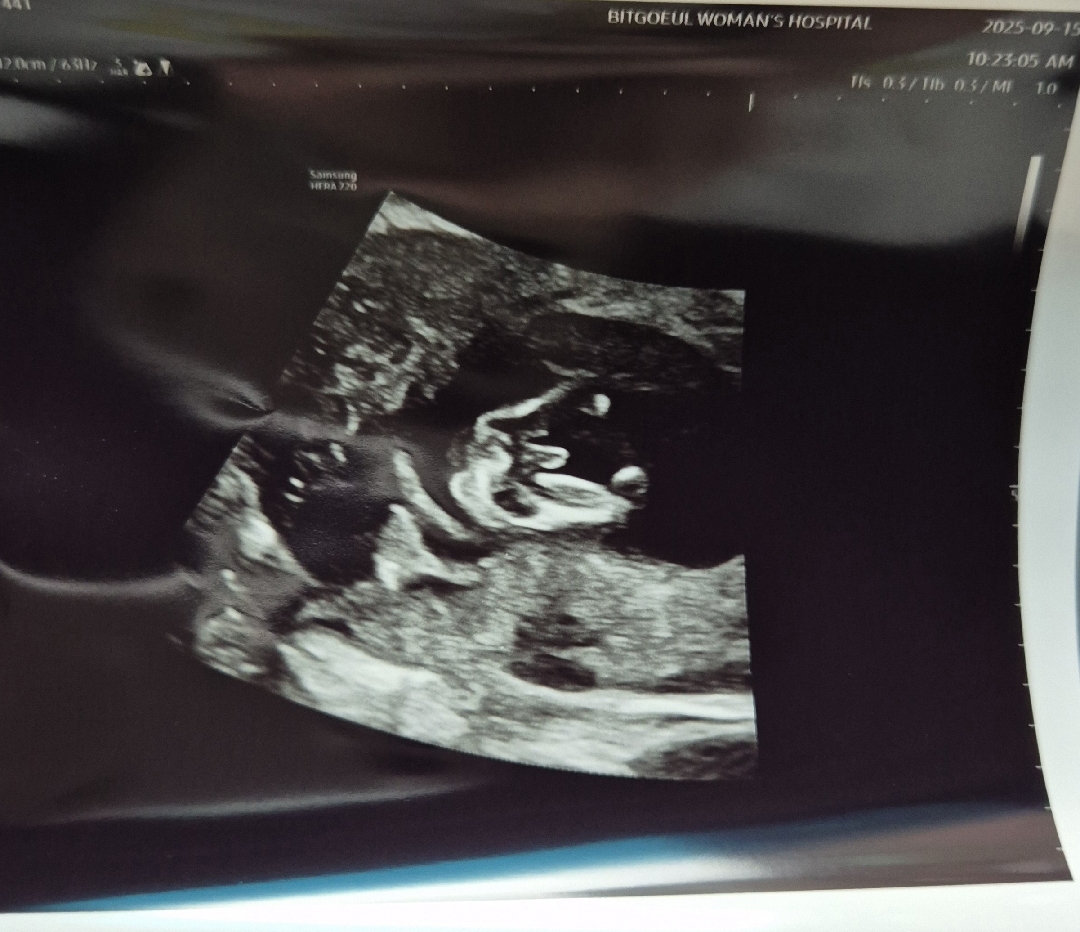

12주 초음파 이정도면 빼박인가요?

선생님께서 16주가 아니라 확정은 아니지만 이정도면 안바뀐다 그랬는데 아들이면 양가 부모님들은 좋아하실거같아서 지금 말해도 될까요?

아뇨~ 16주 정확해지면 말씀드리세요 ㅎㅎ 저희도 저렇게 빼박이였는데 16주여아였어요 12주라면 여아든 남아든 다 빼박 돌기인데 선생님이 왜그러셨을까!!!